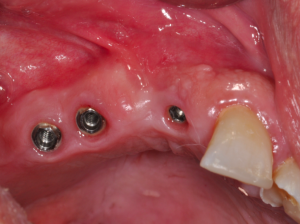

図1 上部構造のない骨結合インプラント